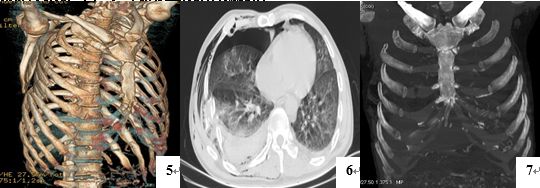

病例 肋软骨骨折1例mr 影像ppt

病例 肋软骨骨折1例mr 影像ppt